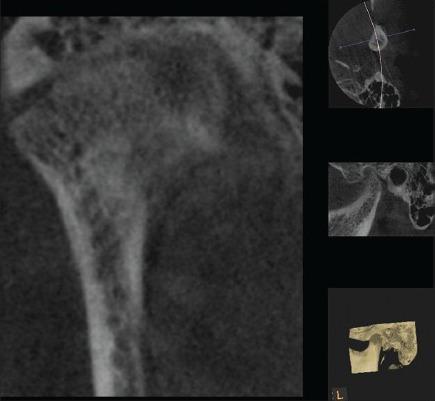

Rheumatoid arthritis (RA) is a chronic, systemic, autoimmune inflammatory disorder that is characterized by joint inflammation, erosive properties and symmetric multiple joint involvement. Temporomandibular joint (TMJ) is very rare to be affected in the early phase of the disease, thus posing diagnostic challenges for the dentist. Conventional radiographs fail to show the early lesions due to its limitations. More recently cone-beam computed tomography (CBCT) has been found to diagnose the early degenerative changes of TMJ and hence aid in the diagnosis of the lesions more accurately. Our case highlights the involvement of TMJ in RA and the role of advanced imaging (CBCT) in diagnosing the bony changes in the early phase of the disease.

类风湿性关节炎(RA)是一种慢性、全身性自身免疫性炎症性疾病,其特征为关节炎症、侵蚀性以及对称性多关节受累。颞下颌关节(TMJ)在该疾病早期很少受到影响,因此给牙医带来了诊断挑战。传统X线片由于其局限性无法显示早期病变。最近发现锥形束计算机断层扫描(CBCT)能够诊断颞下颌关节的早期退行性改变,从而更准确地辅助病变的诊断。我们的病例突出了颞下颌关节在类风湿性关节炎中的受累情况以及先进成像技术(CBCT)在诊断该疾病早期骨质改变方面的作用。